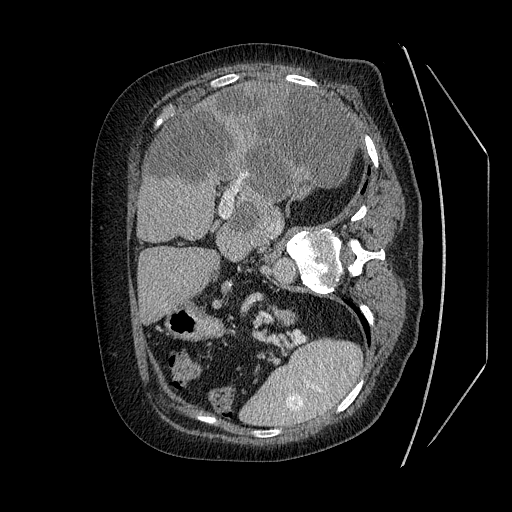

This challenge includes liver segmentation and liver tumor segmentation. The dataset consists of 131 training datasets and 70 testing datasets, all of which are 3D abdominal CT scan images that contain liver. Label maps (annotations) are provided for the training data, but not for the testing data. Participants are required to train their model on the training data, then use the well-trained model to make predictions for the testing data. The prediction can be submitted back to the orgnizer for blind evaluation. An example 3D CT data visualized in different directions is shown in Figure 5.

Refer to caption

Figure 5: Different positions of an example 3D CT data. Upper left: oblique coronal position. Upper right: add annotation (label) to the upper left image, where yellow area is the liver, green areas are the tumors on the liver. Lower left: sagittalia position; lower right: oblique-axial position.